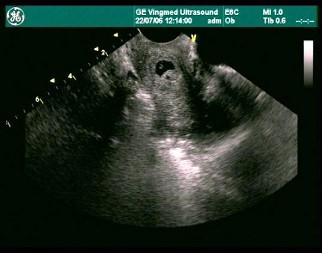

女性,32岁,因停经42天行超声检查,经阴道超声检查提示,初步判断为?(?)A.宫颈妊娠B.宫颈囊肿C.黄体囊肿D.葡萄胎E.以上都不对

问题 女性,32岁,因停经42天行超声检查,经阴道超声检查提示,初步判断为?(?)

选项 A.宫颈妊娠 B.宫颈囊肿 C.黄体囊肿 D.葡萄胎 E.以上都不对

答案 A